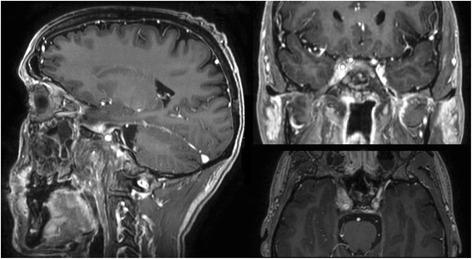

Patient was first diagnosed with locoregionally advanced, non-keratinizing nasopharyngeal carcinoma in 2010. After achieving complete remission following induction chemotherapy and concurrent curative chemoradiation, the patient subsequently developed distant and locoregionally recurrent disease. He received various treatments (neck dissection, radiotherapy to a bony metastasis, palliative chemotherapy, stereotactic re-irradiation of local recurrence) before initiation of anti- PD-1 immunotherapy with pembrolizumab in January of 2016. Following marked local progression 6 months thereafter, we performed re-re-irradiation of the recurrent tumor after careful evaluation and treatment planning. While treatment was well tolerated, the patient subsequently developed marked clinical and radiological signs of immunostimulation with mucosal irritation and swelling of lacrimal and salivary glands as described in the report. Immunotherapy with pembrolizumab was reinitiated, with re- staging showing excellent response with regression of all tumorous lesions. At the time of this report, following near complete recovery of inflammatory symptoms, the patient remains in excellent condition and free from recurrence under treatment with pembrolizumab.

患者于 2010 年首次诊断为局部晚期、非角化性鼻咽癌。在诱导化疗和同期根治性放化疗后达到完全缓解后,患者随后出现远处和局部复发疾病。在 2016 年 1 月开始接受抗 PD-1 免疫疗法帕博利珠单抗治疗之前,他接受了各种治疗(颈部清扫术、骨转移放疗、姑息性化疗、局部复发立体定向再放疗)。6 个月后局部进展明显,我们在仔细评估和治疗计划后对复发性肿瘤进行了再放疗。虽然治疗耐受性良好,但随后患者出现明显的免疫刺激临床和影像学迹象,如报告所述的黏膜刺激和泪腺及唾液腺肿胀。重新开始使用帕博利珠单抗免疫治疗,重新分期显示所有肿瘤病变均有极好的反应,完全消退。在本报告时,在炎症症状几乎完全恢复后,患者在帕博利珠单抗治疗下状况良好,无复发。